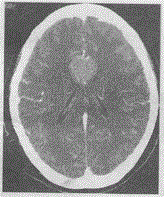

问题 女,60岁.头痛不适,CT强化如图,最可能的诊断是

选项 A.转移瘤 B.脑膜瘤 C.室管膜瘤 D.海绵状血管瘤 E.动脉瘤

答案 B